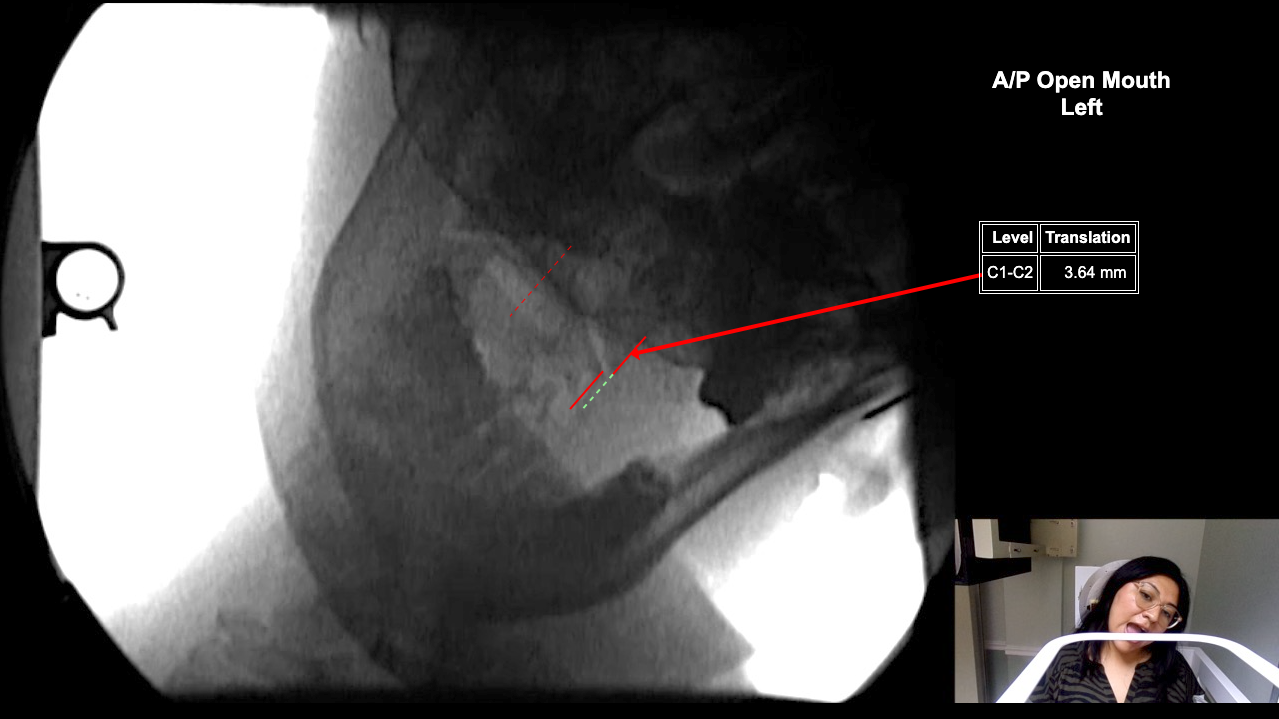

Calibration Set!